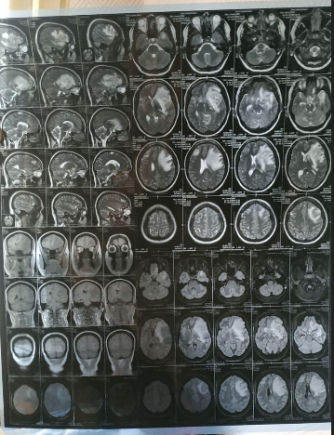

В семью АТОшника Алексея Макухина пришла беда. У его жены обнаружили злокачественную опухоль в головном мозге. Необходима срочная дорогостоящая операция. Друзья семьи просят всех неравнодушных о помощи.

«Друзі, в сім‘ї нашого побратима Алексея Макухи трапилась біда, у дружини діагностували злоякісну пухлину головного мозку. Ціна операції – 20000$, а один день в лікарні – 2000 гривень. Ця сума непідйомна для родини. Олексiй Макуха з серпня 2014 года пішов на війну добровольцем у складі 79 бригади ДШВ (позивний Мак). Приймав безпосередню участь в обороні Маріуполя, а також населених пунктів Мирне, Гранітне, Широкине, Новоселівка, Константинівка. Брав участь у рейді Донецької та Луганської областей у складі 25 та 95 ДШБ. Дуже просимо всіх небайдужих про допомогу!